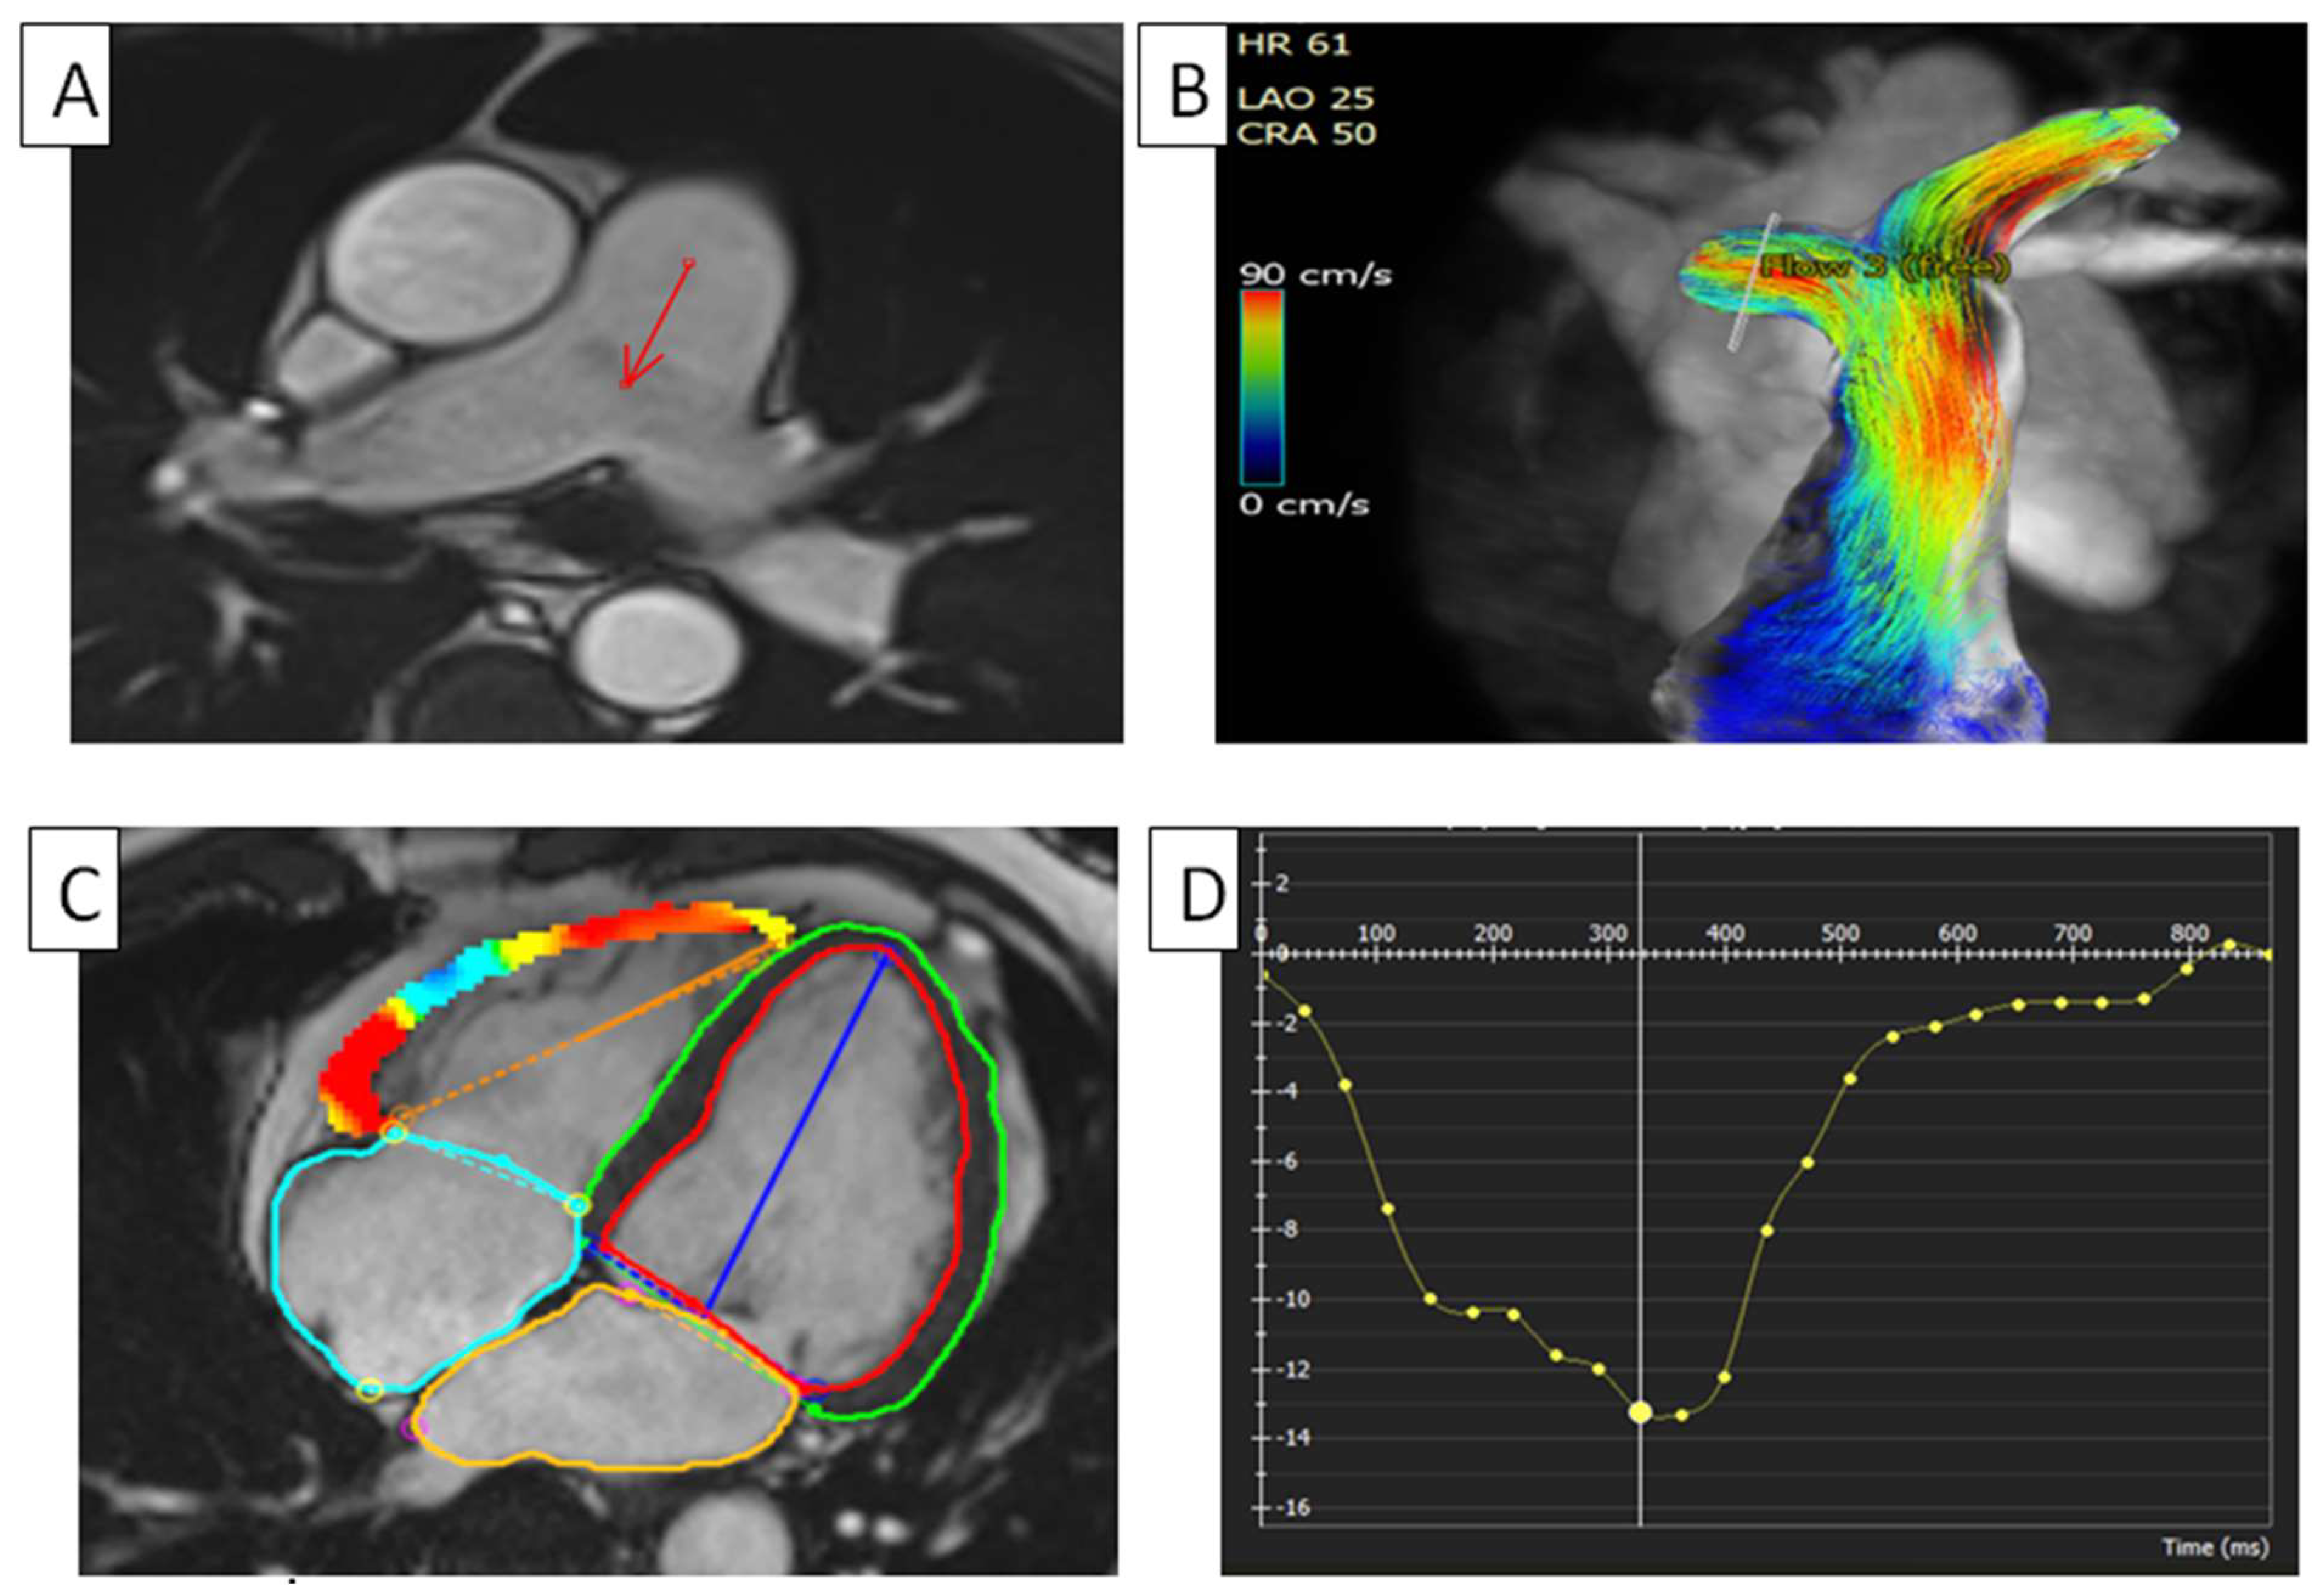

5.1. Pulmonary Artery Hypertension

- McLure, L.E.R.; Peacock, A.J. Cardiac magnetic resonance imaging for the assessment of the heart and pulmonary circulation in pulmonary hypertension. Eur. Respir. J. 2009, 33, 1454–1466. [Google Scholar] [CrossRef]

- Tello, K.; Dalmer, A.; Vanderpool, R.; Ghofrani, H.A.; Naeije, R.; Roller, F.; Seeger, W.; Wilhelm, J.; Gall, H.; Richter, M.J. Cardiac Magnetic Resonance Imaging-Based Right Ventricular Strain Analysis for Assessment of Coupling and Diastolic Function in Pulmonary Hypertension. JACC Cardiovasc. Imaging 2019, 12, 2155–2164. [Google Scholar] [CrossRef]

- Cao, J.; Li, S.; Cui, L.; Zhu, K.; Huo, H.; Liu, T. Biventricular Myocardial Strain Analysis in Patients with Pulmonary Arterial Hypertension Using Cardiac Magnetic Resonance Tissue-Tracking Technology. J. Clin. Med. 2022, 11, 2230. [Google Scholar] [CrossRef]

- Vos, J.L.; Leiner, T.; van Dijk, A.P.J.; van der Zwaan, H.B.; Sieswerda, G.T.; Snijder, R.J.; Post, M.C.; Vonk, M.C.; van Leuven, S.; Vart, P.; et al. Right atrial and ventricular strain detects subclinical changes in right ventricular function in precapillary pulmonary hypertension. Int. J. Cardiovasc. Imaging 2022, 38, 1699–1710. [Google Scholar] [CrossRef]

- de Siqueira, M.E.M.; Pozo, E.; Fernandes, V.R.; Sengupta, P.P.; Modesto, K.; Gupta, S.S.; Barbeito-Caamaño, C.; Narula, J.; Fuster, V.; Caixeta, A.; et al. Characterization and clinical significance of right ventricular mechanics in pulmonary hypertension evaluated with cardiovascular magnetic resonance feature tracking. J. Cardiovasc. Magn. Reson. 2016, 18, 39. [Google Scholar] [CrossRef]

- Koike, H.; Nishimura, T.; Morikawa, M. Quantitative evaluation of pulmonary hypertension using 4D flow MRI: A retrospective study. Heliyon 2024, 10, e31177. [Google Scholar] [CrossRef]

- Reiter, U.; Kovacs, G.; Reiter, C.; Kräuter, C.; Nizhnikava, V.; Fuchsjäger, M.; Olschewski, H.; Reiter, G. MR 4D flow-based mean pulmonary arterial pressure tracking in pulmonary hypertension. Eur. Radiol. 2021, 31, 1883–1893. [Google Scholar] [CrossRef] [PubMed]